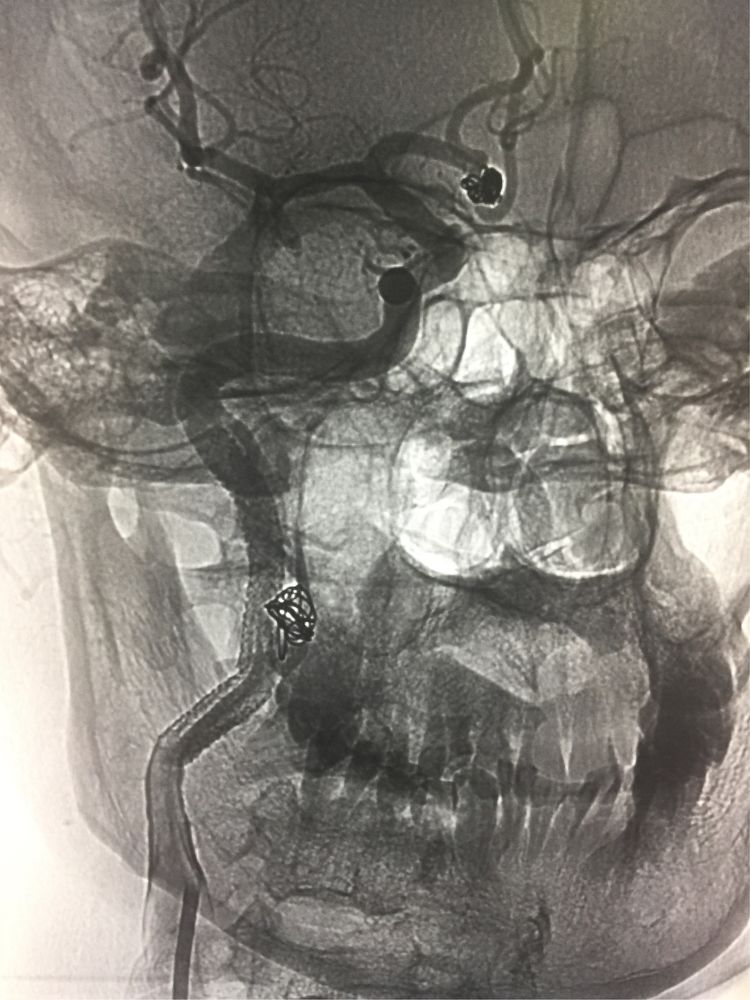

一路重叠铺放三个球扩支架,使动脉夹层内外膜重新贴敷,在夹层破口起始位置放一弹簧圈诱使血栓形成。

骨窗位显示该动脉瘤,因为是位于颈内动脉颅外段,所以手术于局麻下进行即可,术中患者有不适或肢体活动障碍可以随时发现。手术于周五上午化时二小时。术中患者配合,无不适症状。术后卧床二十四小时即下床正常活动,术后三天即出院。